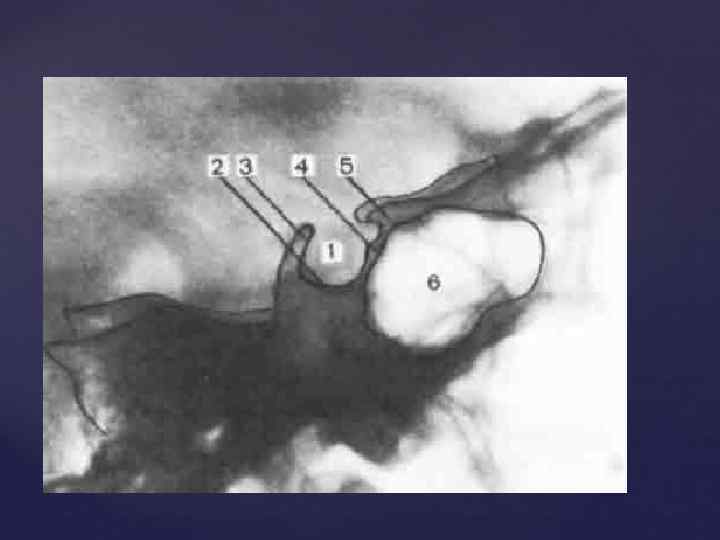

При изучении рентгенограмм черепа необходимо учитывать следующие моменты: 1)Наиболее интенсивную тень дают плотные участки костей (каменистая часть височной кости, скуловая кость). 2) Глазница и воздухоносные полости выглядят как просветления. В боковой проекции хорошо видно турецкое седло. По его размерам и степени сохранности судят о величине гипофиза. Изучение R-гр. черепа

При изучении рентгенограмм черепа необходимо учитывать следующие моменты: 1)Наиболее интенсивную тень дают плотные участки костей (каменистая часть височной кости, скуловая кость). 2) Глазница и воздухоносные полости выглядят как просветления. В боковой проекции хорошо видно турецкое седло. По его размерам и степени сохранности судят о величине гипофиза. Изучение R-гр. черепа